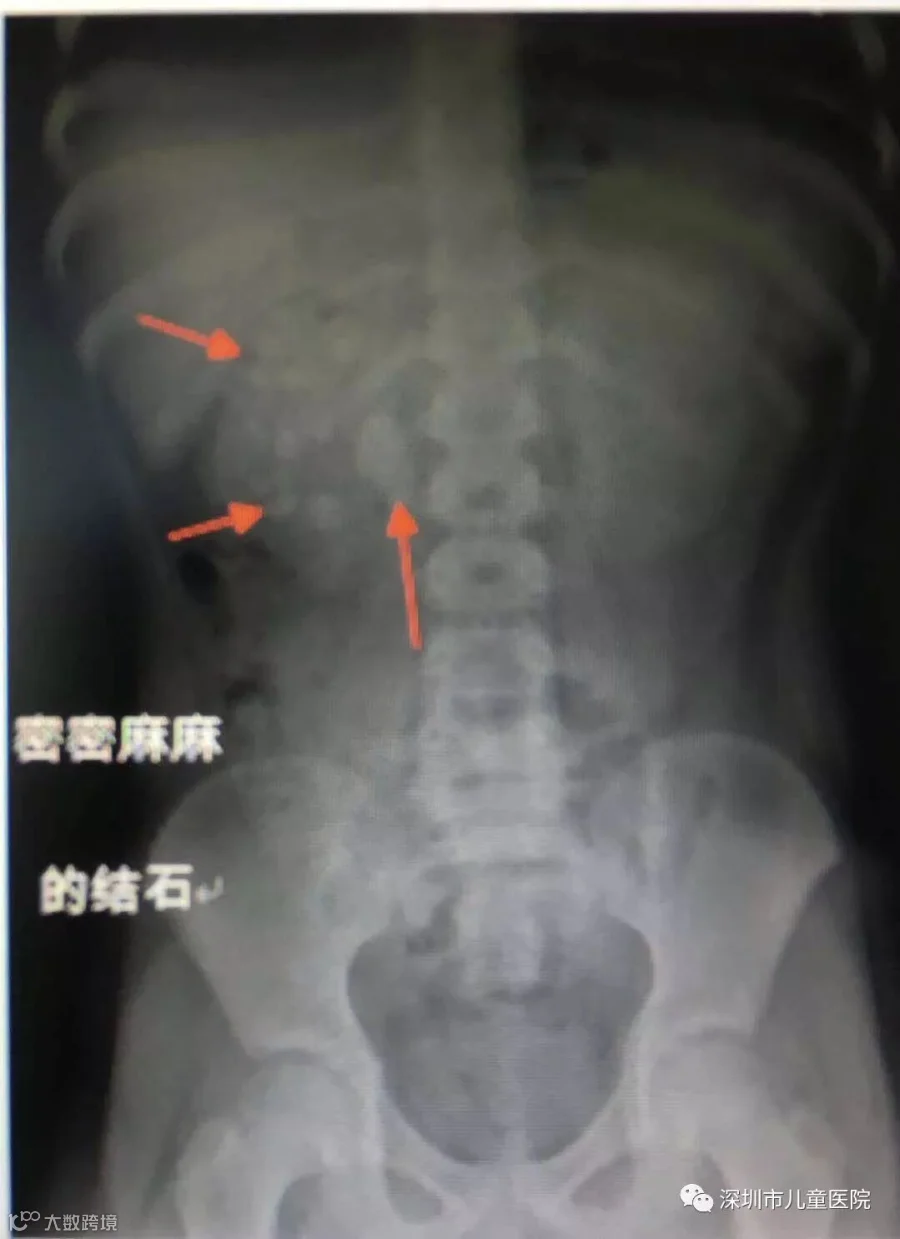

孩子的肾里布满了结石!

感觉到问题严重,当天他们就转到了深圳市儿童医院就诊。一番X光、B超等检查后,见多识广的医生也吓了一跳:

小轩的左肾、右肾内都有结石,右侧肾脏结石尤其多,上中下肾盏及肾盂内都有大量结石堆。

其中,最大一颗结石约2.5×2cm,正好卡在右侧肾盂输尿管交界处,造成了尿路堵塞,导致了右肾中度积水。

现在,小轩双侧肾内有密密麻麻的结石,尤其是卡在右侧肾盂输尿管交界处的结石,竟然有鹌鹑蛋辣么大!可想而知,孩子有多痛。